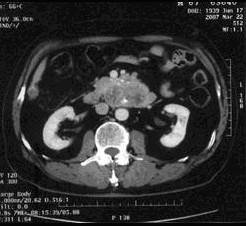

病例1 男,68歲,2006年12月14日,CT掃描發(fā)現(xiàn)胰頭占位性病變,6.0×4.7cm2,腹膜后淋巴結(jié)轉(zhuǎn)移,伴肝內(nèi)多發(fā)轉(zhuǎn)移灶。艾恒+希羅達(dá)化療3療程無效(圖1)。2007年4月5日,開始接受今又生治療,胰腺腫瘤內(nèi)注射今又生1×…今又生治療病例---胃腸腫瘤